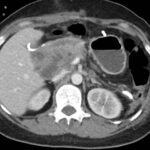

Paciente masculino de 35 años de edad, con antecedentes de tabaquismo, etilismo, consumo de sustancias psicoactivas. Ingresa al hospital de Sanatorio Franchin el 24 de mayo de 2024, donde se constata hipoglucemia severa con buena respuesta al glucosado hipertónico endovenoso. Al examen físico con la típica tríada de Whipple, dado por síntomas neuroglucopénicos de alteración del estado de conciencia, glucemia de 25 mg/dl y alivio sintomático después de la administración de glucosa. El paciente recupera el estado de conciencia y refiere dolor abdominal a nivel de epigastrio, por lo que se le realiza ecografía abdominal, donde se evidencia lesión nodular hipoecogénica en cuerpo del páncreas. Por esta razón se pasa al paciente a tomografía, donde se constata una formación nodular a nivel del cuerpo del páncreas, que presenta un ávido realce en fase arterial con homogeneización de la lesión en tiempo tardío.

Ahora bien, como se mencionaba al principio, el estudio ecográfico es de muy baja sensibilidad y se identifique o no la lesión por este estudio, nuestro siguiente paso en el algoritmo diagnóstico de esta lesión es la tomografía. Esta es la prueba no invasiva inicial, con una sensibilidad del 63% al 83%, y detecta del 70% al 80% de los tumores. Esta debe realizarse como un estudio trifásico: fase arterial temprana a los 30 segundos, fase venosa a los 70 segundos, fase tardía de 3 a 5 minutos. La característica de estos tumores por tomografía es que se presentan como una masa sólida que tiene un ávido realce en la fase arterial, cuyo realce se mantiene y se observa más tenue en la fase venosa y en los tiempos tardíos la lesión se homogeniza.

Para mi caso, y dando una visión general de los métodos de imagen no invasivos en esta revisión retrospectiva, solo a uno de los pacientes se le detectó la lesión por ecografía, donde se visualizó una lesión nodular hipoecogénica en el cuerpo del páncreas. A los demás pacientes se les detectó la lesión por tomografía en estudio trifásico, donde resaltan las características ya descritas por la literatura de lesiones hipervasculares con intenso realce en fase arterial, localizadas en diferentes partes del páncreas, como cabeza, cuerpo y cola.